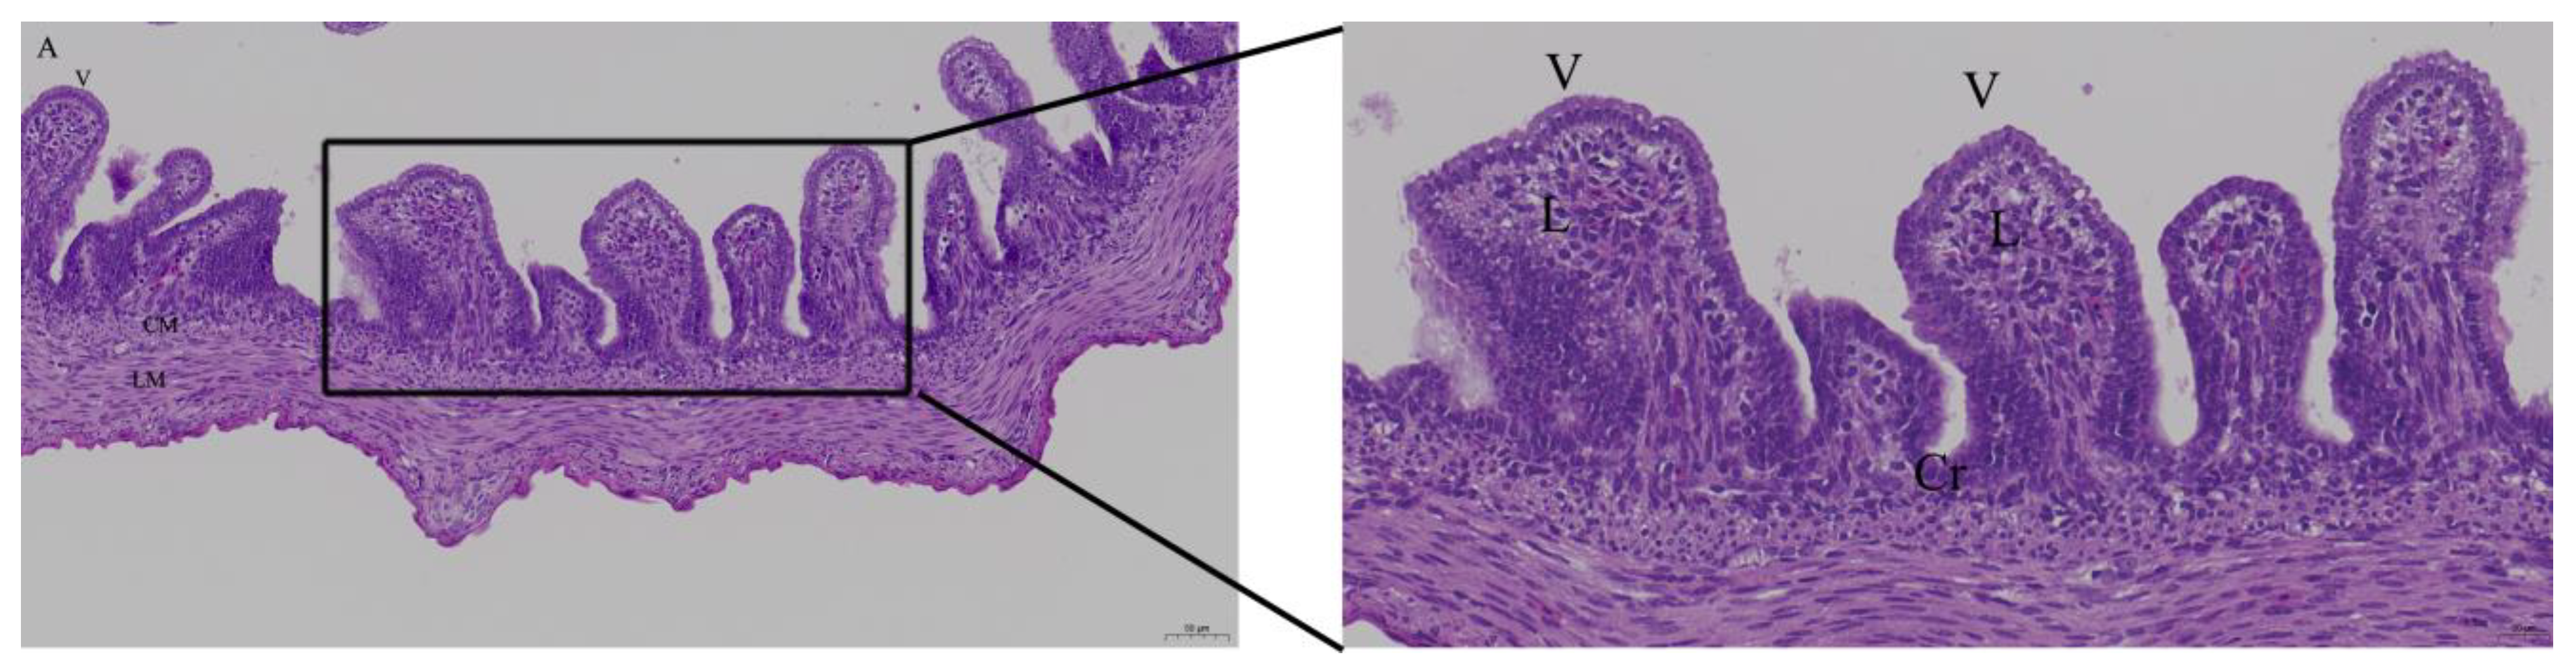

3.2. Effects of Quercetin on Intestinal Mucosa after LPS Induction in Chicken Embryos